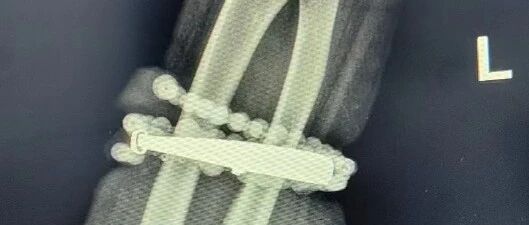

然而,就在兩周前,龔女士的情況急轉直下:手腕不僅疼痛加劇,還出現(xiàn)了明顯的紅腫,甚至有膿液滲出。她這才驚覺——手鐲和串珠,已經有一部分“長”進了肉里,根本取不下來了!

“這是典型的首飾長期壓迫、摩擦,加上細菌感染,引發(fā)的慢性炎癥和肉芽組織增生。”醫(yī)生介紹,此時,手鐲和串珠已經成了一個不斷刺激皮膚、污染傷口的“病灶”,如果不盡快手術取出,感染可能進一步擴散,甚至危及生命或影響手臂功能。

經過一個多小時的手術,醫(yī)生們將手鐲和串珠從厚厚的增生組織中完整剝離出來。目前,龔女士恢復良好,已順利出院。